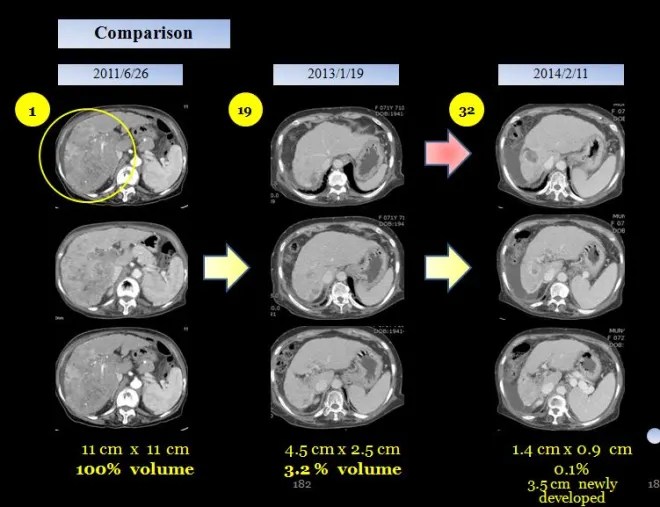

Within 18 months, the hepatic tumor had decreased to approximately 4% of its original volume. In March 2014, I was invited to present at the Korea–China–Japan Integrative Medicine Conference, and in preparation for this presentation, I recommended that the patient undergo a follow-up CT scan after about one year.

Comparison with previous CT (January 19, 2013):The previously noted multiple heterogeneously enhancing hepatic masses have decreased from 2.5 × 4.5 cm to 1.4 × 0.9 cm.

Atrophic change of the right hepatic lobe is again noted.

A newly developed 3.5 cm heterogeneously enhancing mass is observed in segment 8 of the liver.

Tumoral thrombosis in the main and right portal veins has further decreased compared to the previous study, although residual thrombosis remains, and the portal vein shows further contraction.

Liver cirrhosis with splenomegaly is present.

Distal esophageal, paraesophageal, gastric fundal, and perisplenic varices are noted.

A small to moderate amount of ascites is present.No significantly enlarged lymph nodes are observed around the aorta and IVC.

Further decrease in size of previously noted HCCs in the right hepatic lobe.

Newly developed 3.5 cm HCC in segment 8 of the liver.

Decreased extent of tumoral thrombosis in the main and right portal veins.

Liver cirrhosis with splenomegaly, portosystemic collateral vessels, and small to moderate ascites.

By February 2014, the patient’s tumor burden had nearly resolved. The previously existing tumor had decreased to approximately 0.1% of its original size compared to baseline. However, a newly developed 3.5 cm lesion was identified in another region. After this point, the patient did not receive further treatment.